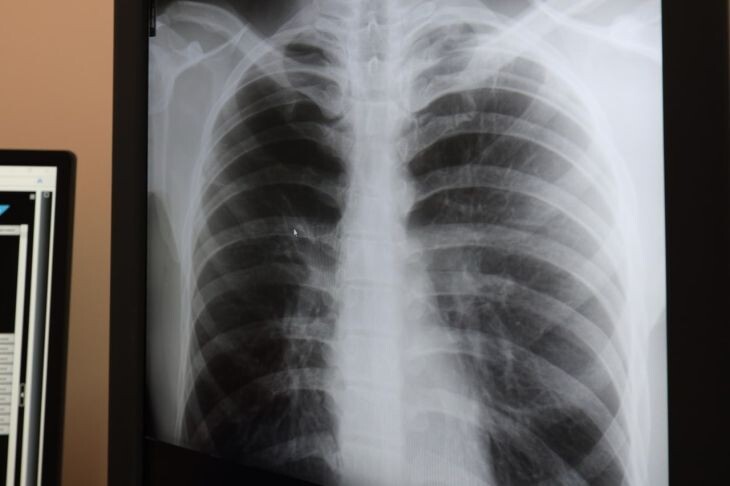

Крымский республиканский клинический центр фтизиатрии и пульмонологии получил новейший аппарат для диагностики туберкулёза — аппарат Bactec. По словам директора учреждения Наиля Аухадиева, он позволяет не только выявить микобактерии туберкулёза, но и определить их чувствительность к противотуберкулёзным препаратам, пишет "Миллет". «Мы полностью обеспечены всем диагностическим оборудованием. Используется вся методология, которая необходима. Буквально 4 февраля мы получили [новый аппарат Bactec, — прим.] Министерство здравоохранение республики и Глава Крыма Сергей Аксёнов выделили деньги, и мы его приобрели», — сказал Аухадиев. Данный аппарат является «золотым стандартом» современной диагностики и лечения туберкулёза. По словам Аухадиева, в Крыму за последние 10 лет заболеваемость туберкулезом сократилась вдвое благодаря эффективному финансированию и диагностике. Однако полностью победить заболевание, подобно оспе, невозможно.

По словам Аухадиева, в Крыму за последние 10 лет заболеваемость туберкулезом сократилась вдвое благодаря эффективному финансированию и диагностике. Однако полностью победить заболевание, подобно оспе, невозможно.